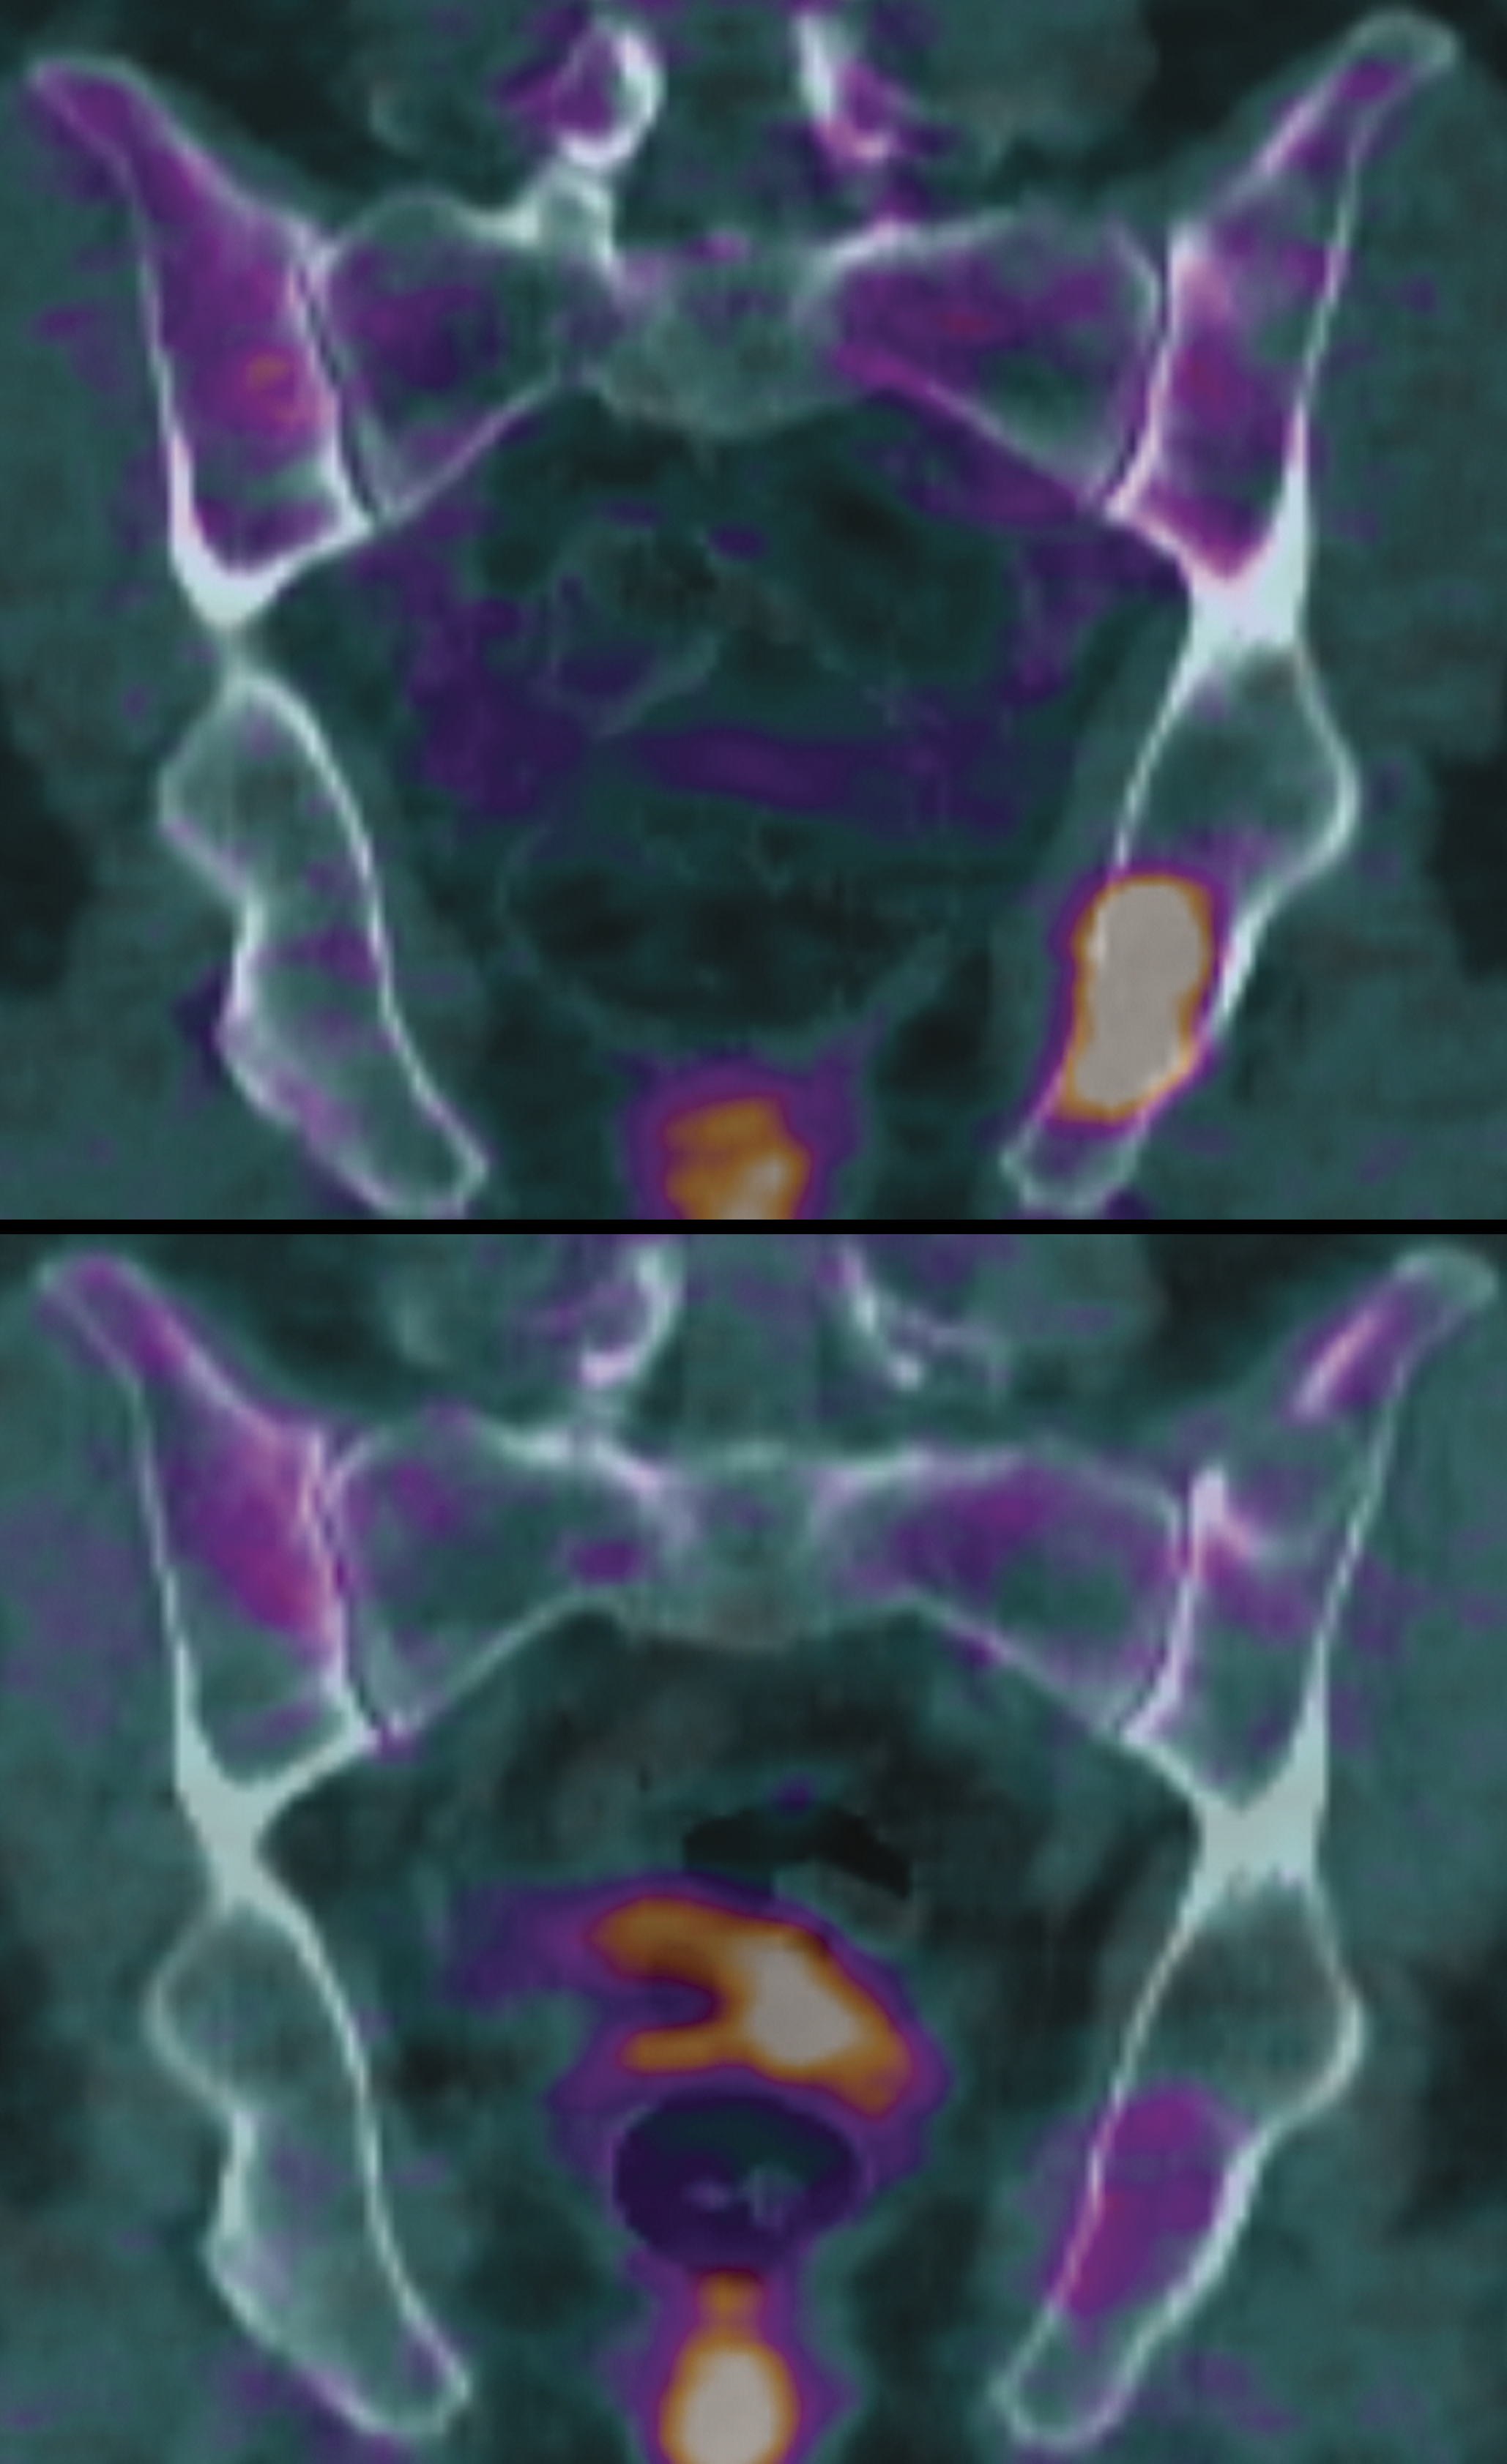

A highly F18-FDG-avid focal myeloma lesion (top image) resolved on follow-up PET-CT examination after 2 cycles of induction therapy (bottom image). When systematically examined as part of Total Therapy 3, such PET-CR status achieved prior to first transplantation was a prognostic indicator of reduced risk of relapse by 49% and of death by 59%, independent of risk as defined by gene array analysis. See the article by Bartel et al on page 2068.